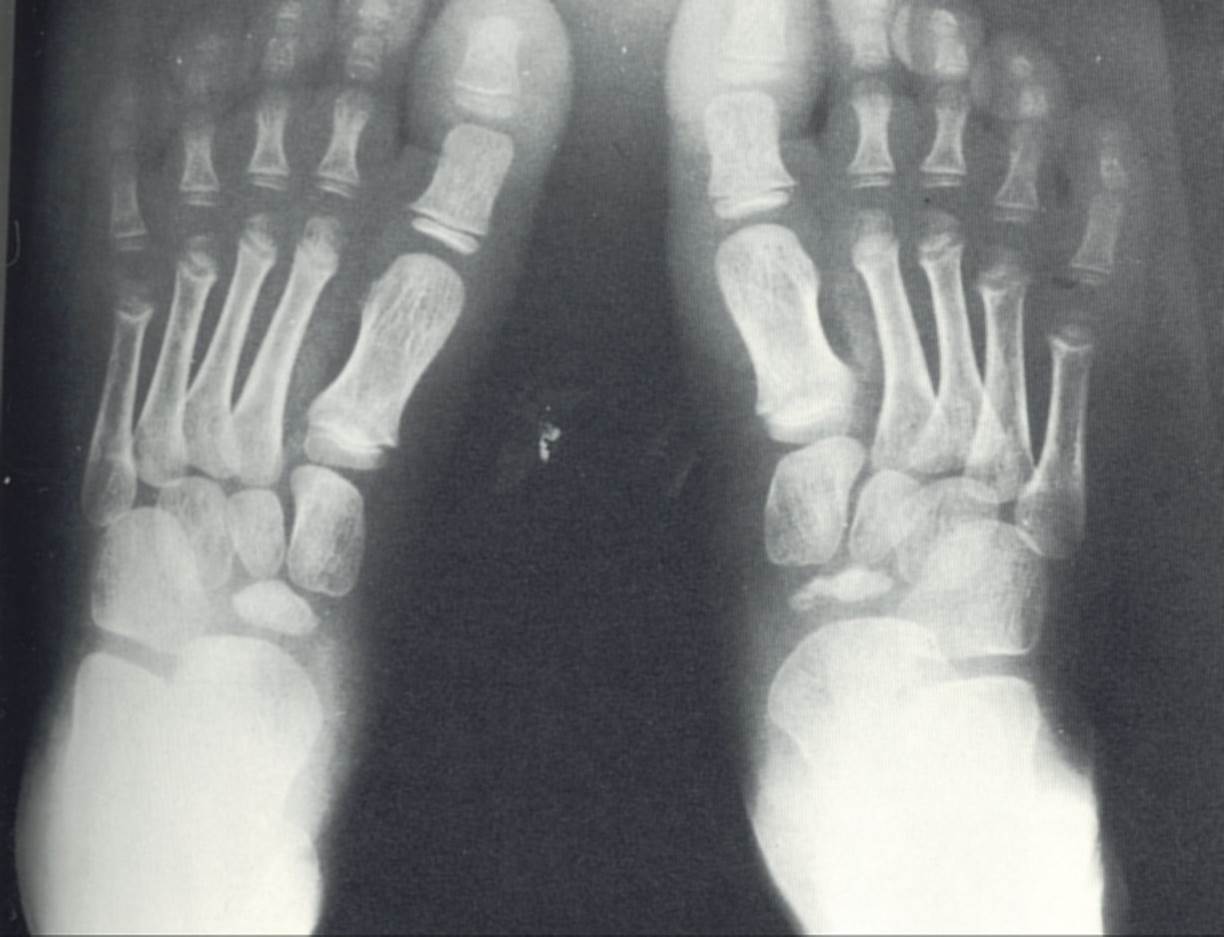

Freibergs infarction

Classifications of freibergs infarction (stages 1-5)

radiographic findings of kohlers disease

treatment of kohlers disease